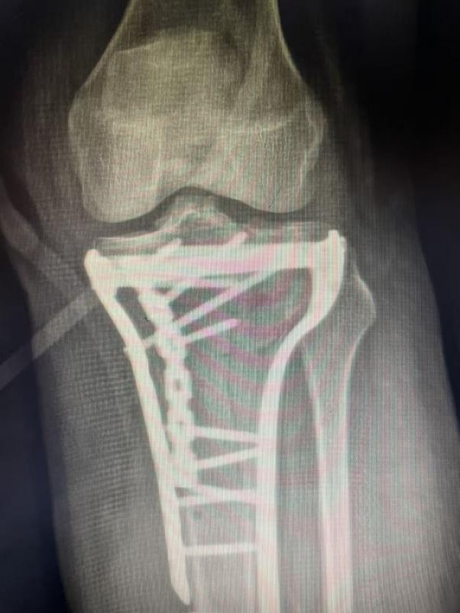

传统治疗手段对于此类骨折往往束手无策,极易导致关节僵硬、畸形愈合、慢性疼痛和继发性关节炎。面对如此复杂的损伤,我院骨科在

南医三院创伤骨科副主任医师杨诚的协助下迅速为张女士成功实施了

胫骨平台骨折切开复位钢板螺钉内固定术。

术后影像显示:患者胫骨平台的关节面高度、宽度及下肢力线得到很好恢复,内固定位置精准牢固。目前,张女士在康复师指导下已开始进行早期的、安全的关节活动度训练,为未来的功能恢复奠定了坚实基础。

(术后图)